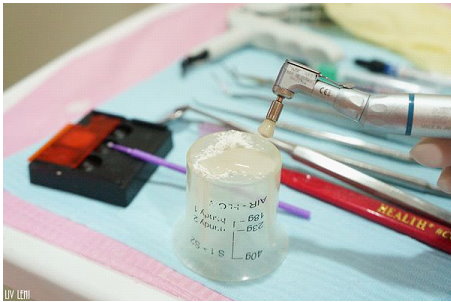

這是清除牙菌斑顯示劑的工具。

每次做完牙菌斑顯影,

診所都會貼心的再幫我們清除乾淨唷(不需要自己動手刷的要命XD)